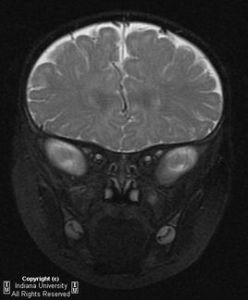

患病兒童1、縱裂接近三腦室前部(胚胎期縱裂與透明隔間腔相通,以後被胼胝體嘴封閉,若嘴不發育則縱裂與透明隔間腔相通,直達三腦室前部。嘴部發育最晚,無論胼胝體發育不全或不發育均累及胼胝體嘴部。所以縱裂與三室前部相通是最常見的表現。

2、胼胝體全部或部分缺如,部分缺如往往發生於胼胝體壓部。海馬,前或後連合缺如。

3、側腦室前角向外移位,側腦室內側緣有凹陷的壓跡。原因是原先連線兩側半球的前部胼胝體缺如,那些本來橫向連線兩側半球的纖維現在呈縱向排列,位於側腦室內緣,壓迫側腦室,形成壓跡。畸形的兩側腦室前角彼此分離,形成蝙蝠翼狀。

4、側腦室體分離,相互平行,主要見於橫斷面圖象上,可能是輕度胼胝體發育不全僅有的表現。

5、胼胝體壓部缺如,使側室三角區擴大。

6、大腦半球內側面的腦溝呈放射狀排列(在矢狀面圖像上)。

7、海馬發育低下,導致側室顳角擴大。深部白質發育不良也是側室擴大的原因。

8、第三腦室位置升高,並呈囊狀擴張,使兩側大腦內靜脈分離。

9、在兩側半球之間的縱裂中形成大的囊腫,囊腫和第三腦室是分離的,與側腦室之間可有或無交通。囊腫可以只位於大腦鐮的一側,或跨大腦鐮,位於大腦鐮兩側。

10、胼胝體膝部可合併脂肪瘤,脂肪瘤也可以延伸至胼胝體的所有部分。